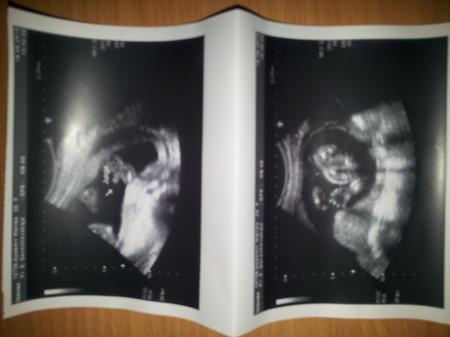

Mein kleiner mann bin so verliebt. Guckt euch mal die bilder an, so als wenn er sagen würde, so mama ich mach jetzt mal die beine breit guck dir das an Meine frauenärztin meinte nur ohh ist das ein stolzer junge oh ne

Haha stolzer junge :)